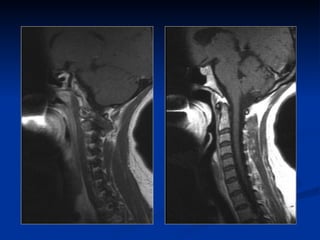

IRM cervicale Technique « Scowt view » Séquence sagittale TSE T2 Séquence sagittale TSE T1 Coupe axiale EG T2 Séquence EG à effet myélographique Injection de PC non systématique

IRM cervicale Technique« Scowt view » Séquence sagittale TSE T2 Séquence sagittale TSE T1 Coupe axiale EG T2 Séquence EG à effet myélographique Injection de PC non systématique